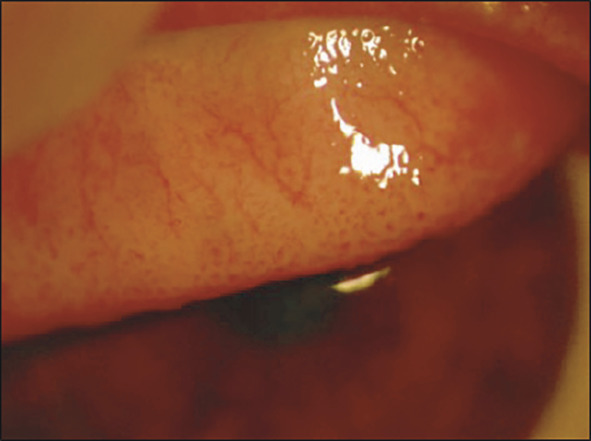

• des papilles géantes, tarsales supérieures surtout (fig. 2) ;

• des grains de Trantas limbiques : amas superficiels blanchâtres d’éosinophiles, au niveau du limbe, qui ressemblent à des grains de mil (fig. 3).